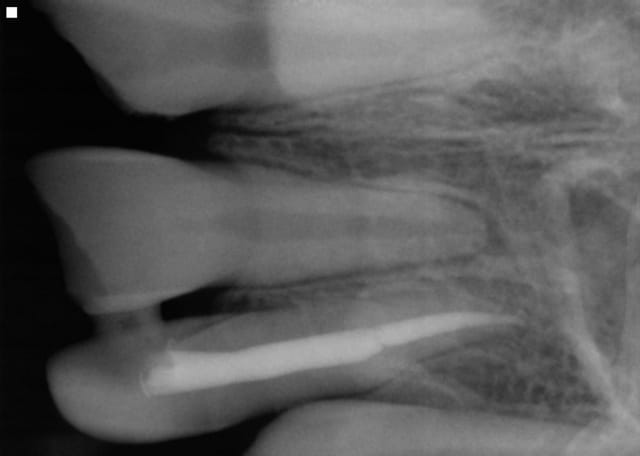

Bilan: 11 21 fracturées mais la 22 est semi expulsée, collée à la gencive. Je me dis que je vais faire une réimplantation mais je découvre, en la prélevant, qu'elle a été fracturée . Reste donc la moitié de la racine que j'arrive à extraire avec une curette en laissant l'os et la racine intacte. J'ai traité le canal et recollé les deux morceaux et réimplanté.

- Pour la 22 : impossible de prédire avec certitude la suite. Une résorption externe est très probable avec une perte de la dent dans un délai de 6 mois à 6 ans.

Il faudra surveiller régulièrement l'absence d'infection : une perte d'os compliquerait l'implant à venir. Avulsion au moindre signe (radio, clinique) infectieux.

Pour la contention, il me semble voir sur la radio un plot de résine entre 21 et 22. Cela ne tient jamais et saute rapidement dès que l'enfant mastique. Il aurait mieux valu une contention avec un fil souple qui solidarise des dents dans des plans différents : en l'absence des canines, contention de 4 à 4. Et alimentation molle sur une semaine.

Pour le collage, j'ai, autant que possible, placé l'adhésif avec une microbrush en évitant les bords ext, photo, puis placé un compo fluide avec une microbrush toujours à distance des bords externes. J'espère qu'ainsi il y aura un minimum de compo au contact de l'os.

Je n'ai pas cureté la racine, simplement soigneusement nettoyée pour tenter de préserver les fibres.